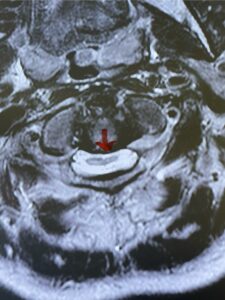

Fig. 4b: Axial T2-weighted cervical MRI demonstrating severe spinal cord compression from atlanto-axial instability (red arrow)

Cervical x-rays revealed a significantly increased atlanto-axial interval (Fig. 5) On review of her imaging studies it was noted that the right C2 isthmus was very thinned by the vertebral foramen (Figs 6a, b, and c) which would make an attempt at placing a C2 pars screw dangerous. A decision was made to perform an occipital-cervical fusion because only possible unilateral fixation and an extensive C1 laminectomy to be performed eliminating a fixation point if a more traditional C1-C2 was performed. Even if C1 lateral mass screws were able to be placed one could only perform a unilateral screw construct fixation to C2. We performed an occipital cervical fusion down to C4 to get enough inferior fixation and C1 laminectomy. The decompression went well. We placed a left unilateral pars screw and bilateral C3 and C4 lateral mass screws. We placed three 12 mm screws in the midline keel (Fig. 7). Postoperatively the patient had all around improvement in her symptoms and did not qualify for rehab. Her post op films at 6 weeks (Fig. 8)